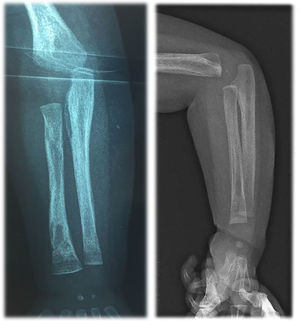

Blood tests showed: aregenerative normocytic anaemia (7.7 g/dL of hemoglobin), elevated C-reactive protein (160 mg/L), elevated white blood cells (28 G/L) with a high lymphocytosis (13 G/L). Liver tests showed mild cytolysis without cholestasis. Chest X-Ray was normal. Urine cytology and culture, lumbar fluid tests and culture, repeated blood cultures, and viral serologies were negative. Empirical antibiotic treatment with amoxicillin/clavulanate was initiated, then replaced by cefotaxime for six days without improvement. Because of the persistence of fever despite antibiotic treatment, other infectious causes were investigated: a 99mTc-diphosphonates scintigraphy showed a left wrist hyperfixation, and the further wrist X-Ray diagnosed a periostitis and osteomyelitis of the radius (Fig. 1), but the lesions were too small for biopsy. The antibiotics were then replaced by cefazolin and clindamycin for six days. MRI of the left wrist did not confirm osteomyelitis; so, antibiotics were discontinued. Echocardiography showed an intracardiac mass (15 × 8 mm) on the posterior wall of the right atrium extending to the origin of the superior vena cava. Cardiac MRI showed an intracardiac mass attached to the posterior wall and interatrial septum with a T2 hypo-signal, without enhancement after gadolinium injection (Fig. 2). Three hypotheses were considered: a right atrial myxoma (unlikely, however, due to non-enhancement after gadolinium injection), thrombosis of the superior vena cava, or a large Chiari network, which is a fenestrated, net-like embryonic remnant of the sinus venosus valves. One month later, in view of the finding of multifocal involvement, and persistent fever with persistent lymphocytosis elevation of liver enzymes, toxoplasmosis and syphilitic serology were performed. The Treponemal Hemagglutination Assay (TPHA) was superior to 10,240 and the VDRL (non-treponemal agglutination assay) was equal to 1:32. A new test on the mother revealed positive VDRL (1:8) and TPHA (> 10,240) tests. This child was born into a family with a low economic and social status, and the mother later reported several sexual partners. The infant was treated for 10-days with penicillin-G, administered at a dose of 250,000 units/kg/day, as recommended.4 Fever subsided on the first day, but a study of lymphocyte count and CRP showed that the inflammation had not been resolved. Thirteen days after the end of antibiotics, a second antibiotic course was prescribed: penicillin-G, administered at a dose of 150,000 units/kg/day for 15-days. Then a third cure was prescribed 10-days after the end of the second one, with the same posology. The effect of this prolonged antibiotic therapy led to a negative CRP and good infant health. However, the right atrial mass did not decrease and hyperlymphocytosis persisted. The infant was discharged after 4-months in hospital.